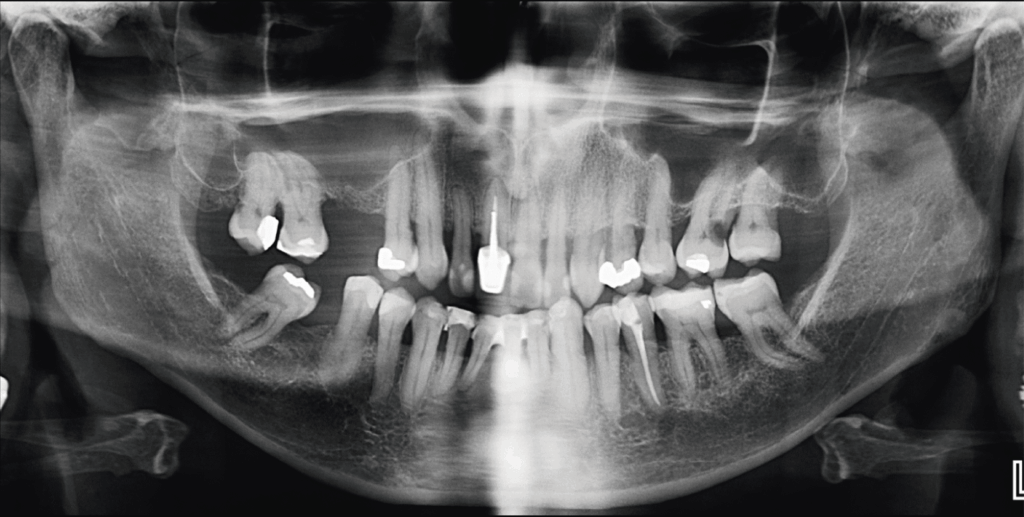

Paciente masculino de 70 años de edad acude a IDM- Sede Miraflores para realizarse una tomografía por un dolor leve que sentía en el primer cuadrante, a la evaluación de la radiografía panorámica se observa edentulismo parcial, la neumatización de ambos senos maxilares, reabsorción ósea moderada del proceso alveolar, las piezas 18 y 17 con restauraciones coronarias amplias, así como piezas dentales con tratamiento de conductos (subextendida en la pieza 11) y la presencia de una lesión cariosa cervicodistal amplia en la pieza 26.

Radiografia Panorámica